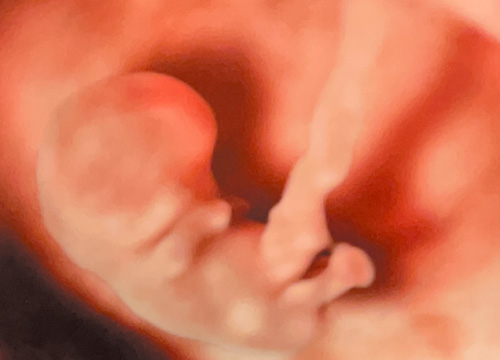

《 超音波検診 》

当院では4D超音波診断装置を導入しております。リアルタイムでお腹の赤ちゃんの様子がご覧いただけます。又、超音波検査で撮影された胎児の成長記録をUSBやSDカードに収録してお渡しするサービスも実施しています。但し、セキュリティの観点上、USBとSDカードは当院にてご購入いただいたものに限らせていただきます。

GE最新エコーを導入しており、胎児の血流情報も高感度で描写するパワードプラも備えています。